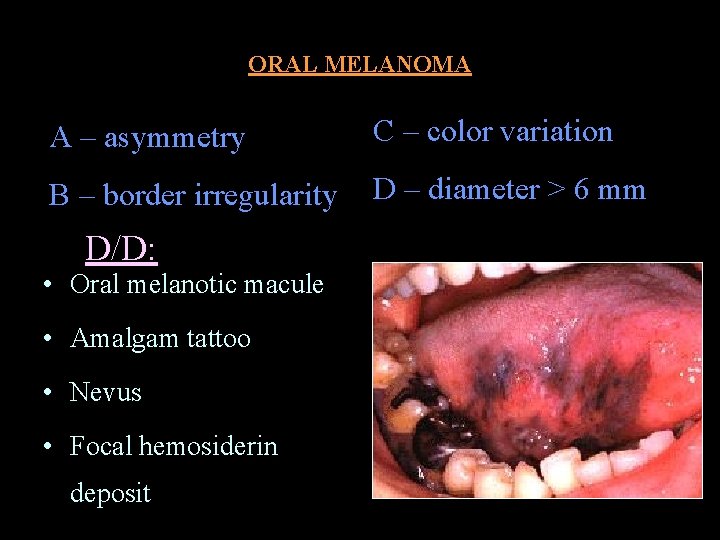

ORAL MELANOMA • Melanoma malignant tumor of nevus cells • Have a nodular component • Slightly more in males • 4 presentations – pigmented macule – pigmented nodule – large pigmented exophytic lesion – Amelanotic variety • Color mucosal pink – brown – blue – black • May ulcerate but no rolled out borders

• Rate of growth slow • Vertical phase rapid • Usually painless • Rapid infiltration fixed to underlying tissues • Spread lymphatic & hematogenous routes • Many develop from nevi

ORAL MELANOMA A – asymmetry C – color variation B – border irregularity D – diameter > 6 mm D/D: • Oral melanotic macule • Amalgam tattoo • Nevus • Focal hemosiderin deposit